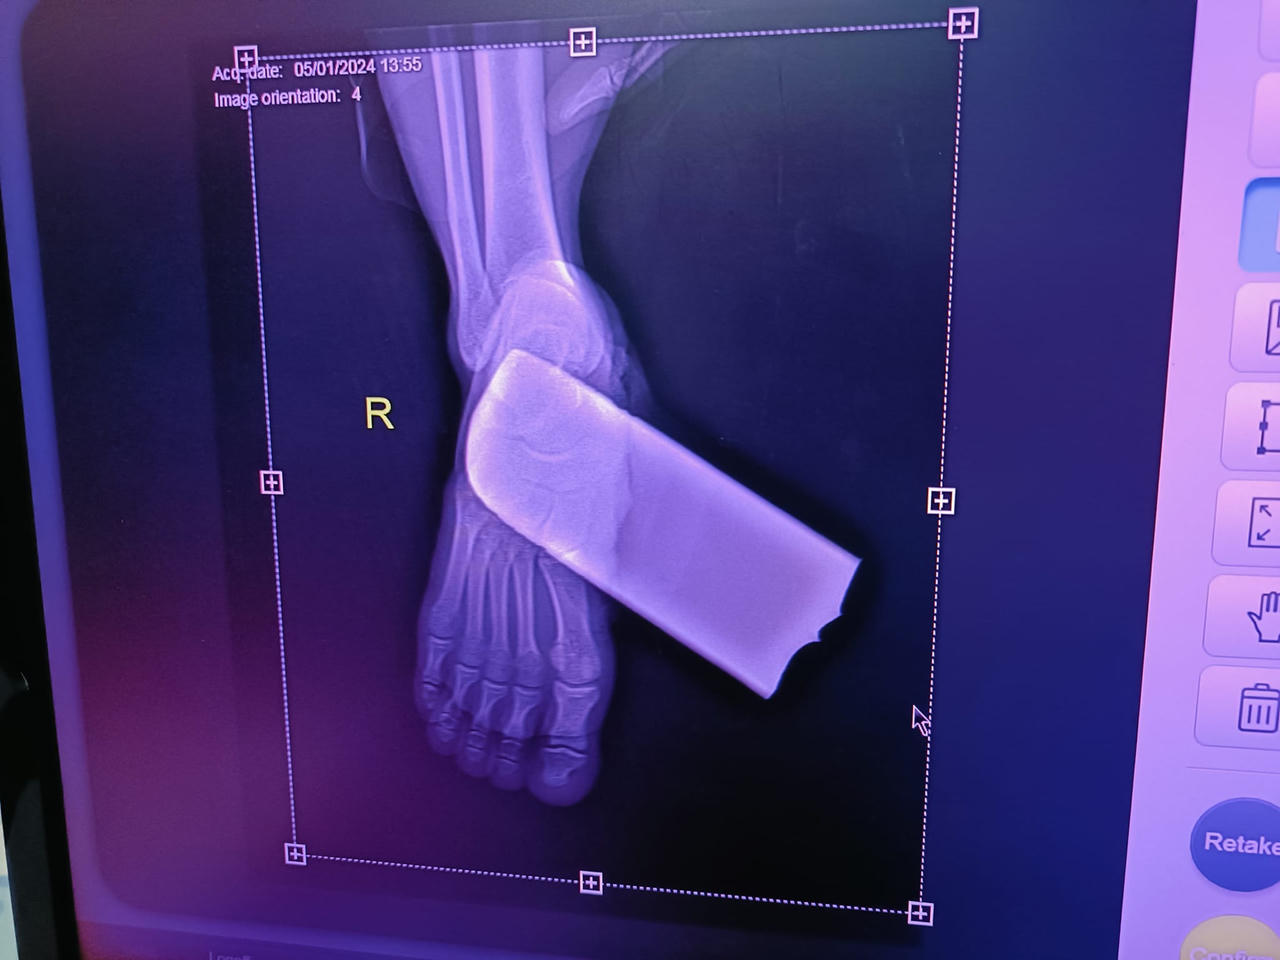

Hình ảnh chụp X-quang bàn chân của bệnh nhân bị lưỡi cưa của máy cắt cỏ găm vào. |

Bác sĩ điều trị cho biết, bệnh nhân bị lưỡi máy cắt cỏ gãy bắn găm vào bàn chân phải gây tổn thương đứt cơ gan bàn chân và mạch máu. Kíp mổ đã phối hợp với kíp gây mê hồi sức tiến hành lấy dị vật, cầm máu, cắt lọc vết thương bị dập nát và khâu phục hồi bàn chân thành công.